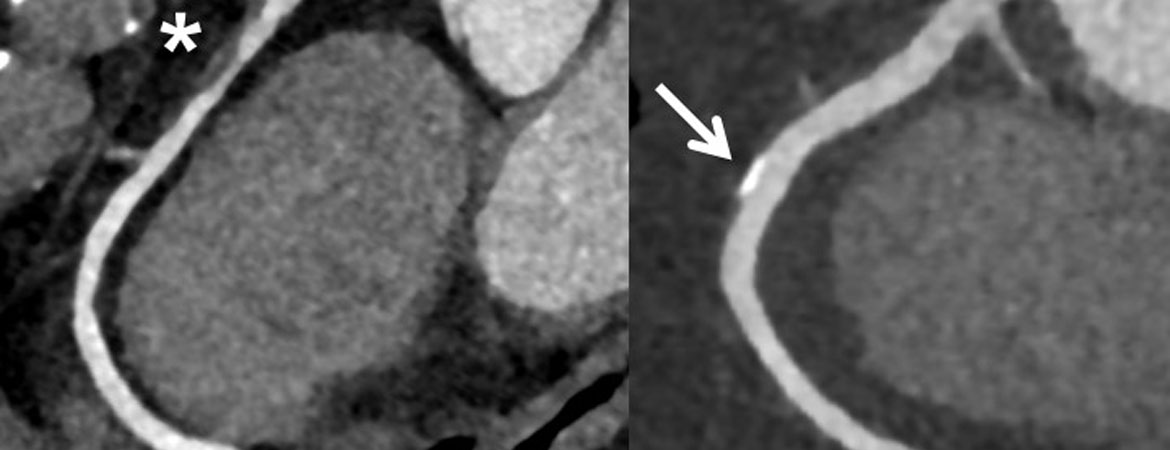

Evelyne Neurauter, Sebastian Leschka, Simon Wildermuth, Niklas F. Ehl, Lucas Joerg, Hans Rickli, Micha T. Maeder (Author) Use of coronary computed tomography angiography in clinical practice – single centre experience in Switzerland in light of current recommendations based on pretest probability considerations Fulltext PDF Fulltext HTML